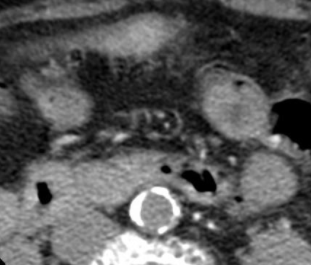

Cas

lereiche lerieche fontaine aorte aortique thrombus embol embolie occlusion iam syndrome lereiche